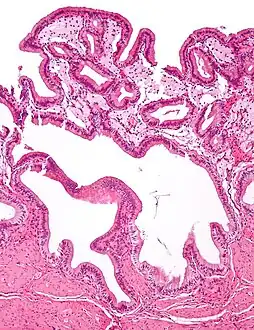

Cholesterolosis of gallbladder

In surgical pathology, strawberry gallbladder, more formally cholesterolosis of the gallbladder and gallbladder cholesterolosis, is a change in the gallbladder wall due to excess cholesterol.[1]

The name strawberry gallbladder comes from the typically stippled appearance of the mucosal surface on gross examination, which resembles a strawberry. Cholesterolosis results from abnormal deposits of cholesterol esters in macrophages within the lamina propria (foam cells) and in mucosal epithelium. The gallbladder may be affected in a patchy localized form or in a diffuse form. The diffuse form macroscopically appears as a bright red mucosa with yellow mottling (due to lipid), hence the term strawberry gallbladder. It is not tied to cholelithiasis (gallstones) or cholecystitis (inflammation of the gallbladder).[2]